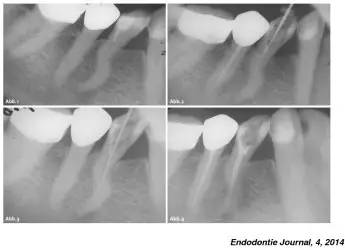

神奇的根管变异侧穿

一例前磨牙根管侧穿再治疗!